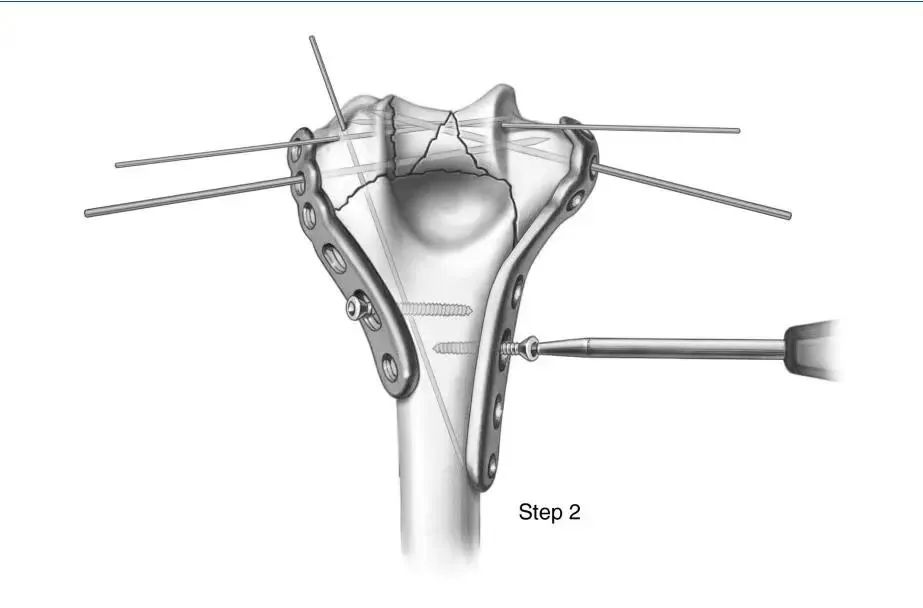

第二步:钢板敷贴和临时固定。将内侧和外侧预成型钢板放置并固定在肱骨远端,同时通过每个钢板的2号孔(从远端到近端编号)、上髁和远端骨块插入一个光滑的2mm或2.5 mm科氏针,以维持钢板与远端骨折的临时固定。

在每个钢板的开槽孔(5号孔)中放置一个螺丝钉,但没有完全拧紧,在压缩过程中为钢板留出了一些向近端移动的自由。由于每个接骨板的下表面在干骺端和骨干端都是管状的,所以只需稍微拧紧开槽孔中的螺钉,就可以提供良好的整个肱骨远端的临时固定。